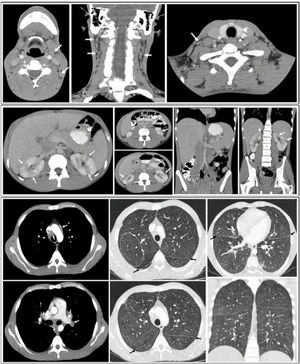

The contrast-enhanced CT of the chest revealed multiple lymphadenopathies in the mediastinum, particularly in the bilateral parahilar, prevascular, pretracheal, and subcarinal regions. Thickening of the bronchial walls was noted, predominantly in the central area and extending toward the lower lobes; multiple micronodules with soft-tissue density forming a miliary pattern, with diameters less than 3 mm in both lung parenchyma were noted.

Contrast-enhanced abdominal CT revealed para-aortic, interaortocaval, and retroperitoneal adenomegalies, along with hepatomegaly featuring multiple small hypodense nodular lesions suggestive of microabscesses. Areas of non-enhancement with a wedge-shaped morphology were also observed in both kidneys, indicating focal nephritis (Fig. 4).

CT scans of the neck, thorax, and abdomen: A) Presence of bilateral cervical adenomegalies. B) Presence of multiple adenopathies in the mediastinum, mainly in the bilateral parahilar, prevascular, pretracheal, and subcarinal regions. Thickening of the bronchial walls, predominantly in the central area and towards the lower lobes, in addition to multiple micronodules with soft-tissue density that formed a miliary pattern, with diameters less than 3 mm, present in both lung parenchymas. C) Nodular lesions in the liver and kidney, with hepatomegaly and splenomegaly.